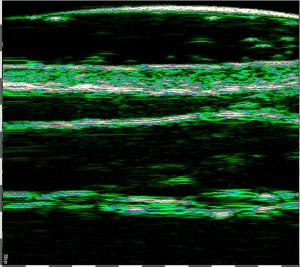

Η μέτρηση του πάχους του χορίου με Υπέρηχο Υψηλής Συχνότητας (HFUS) και η αξιολόγηση της κατάστασης του δέρματος είναι απαραίτητες για την επιλογή των τακτικών διαχείρισης του ασθενούς με επαρκή στοχευμένη θεραπεία. Τα αποτελέσματα της μέτρησης HFUS δείχνουν το βάθος και το πάχος του ιστού-στόχου, καθώς και τι είναι απαραίτητο για την επιλογή των βέλτιστων παραμέτρων της θεραπείας (διείσδυση, βάθος και ένταση).

Πάχος Επιδερμίδας 0.16mm. Lasers: KTP, PDL, Erbium

Πάχος Χορίου 1,3mm. Lasers: CO2, Nd:YAG, Diode 800nm, Alexandrite, Ruby

Ιδανικό βάθος επίδρασης για αυτόν τον ασθενή και σε αυτή την περιοχή είναι 1,4-1,7mm.

Επιδερμίδα, πάχος 0,16 mm. Λέιζερ: KTP, PDL, Erbium

Χόριο, πάχος 1,3 mm. Λέιζερ RF: CO2, Nd:YAG, Διοδικό 800 nm, Αλεξανδρίτης, Ρουμπινίου.

Το βέλτιστο βάθος επίδρασης, για αυτόν τον ασθενή, και σε αυτήν την τοποθεσία, είναι 1,4-1,7 mm.